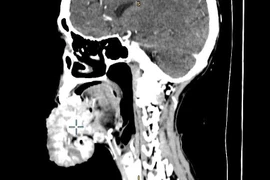

Bạc Liêu: Phẫu thuật cứu kịp thời bệnh nhân bị áp xe vùng cổ nguy hiểm ảnh 2Khối áp xe lan tỏa ở vùng cổ trái. (Ảnh: Chanh Đa/TTXVN)

Qua thăm khám, thực hiện các biện pháp cận lâm sàng cần thiết, các bác sỹ chẩn đoán bệnh nhân bị áp xe cổ lan tỏa.

Ngay lập tức, các bác sỹ đã tiến hành phẫu thuật. Ca phẫu thuật diễn ra trong 50 phút. Các bác sỹ đã thực hiện mở cạnh cổ bên trái dẫn lưu áp xe, tránh gây biến chứng chèn ép đường thở và tránh nhiễm trùng lan tỏa vào trung thất.